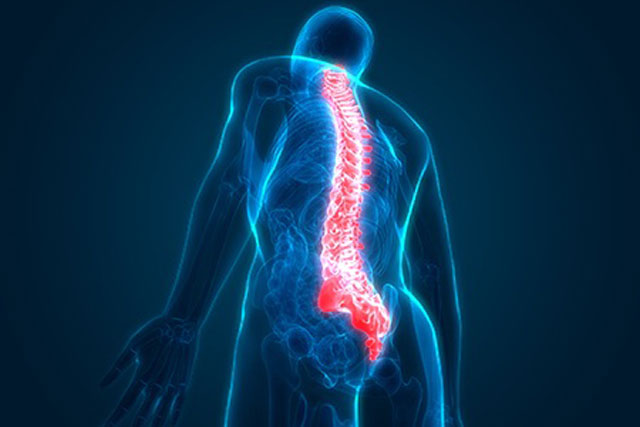

We understand that pain and injury don’t just affect the body—they affect your daily life, your mood, and your independence. That’s why our approach focuses on more than just symptom relief. We work closely with each patient to identify the root cause of their condition, create tailored rehabilitation programs, and empower them with education and exercises for long-term recovery.Our services include advanced physiotherapy for musculoskeletal injuries, post-surgical rehabilitation, sports recovery, neurological conditions, and chronic pain management.